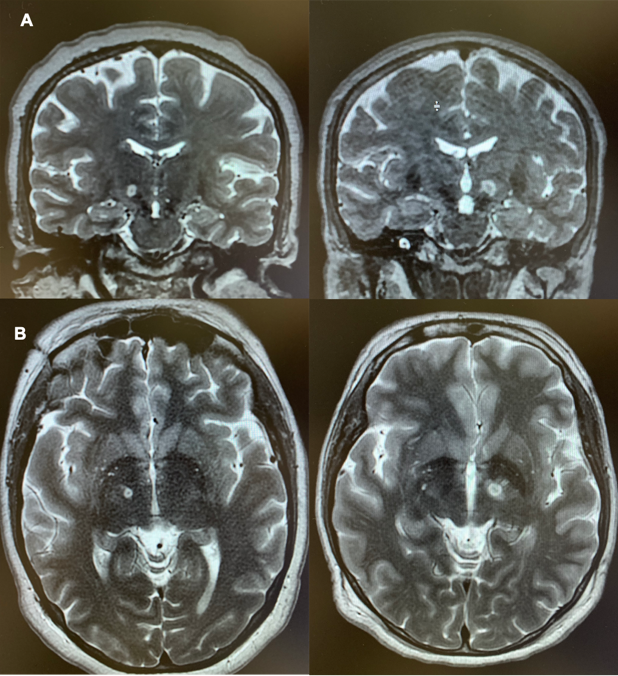

Figure 1. Magnetic Resonance Images in Two Patients Immediately After MRgFUS Subthalamotomy. Coronal (A) and axial (B) T2-weighted views obtained immediately after the procedure. The site of the lesion is recognizable by a heterogeneous central area corresponding to tissue necrosis, which is typically hypointense (black) on T2-weighted images. This zone is delimited by a rim of perilesional cytotoxic edema, hyperintense (white) on T2-weighted images. An additional hyperintense area on T2-weighted imaging corresponds to edema spreading within the white matter surrounding the subthalamic nucleus.